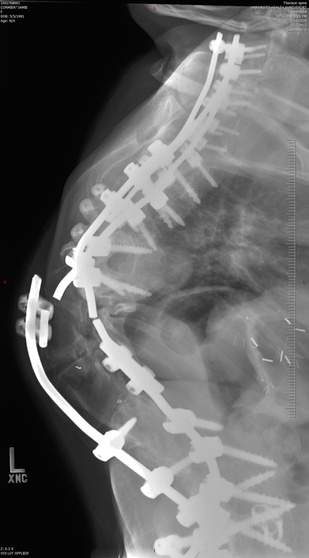

Jamie Cormier, now 27 years old, first shared her story with us when she was 21. Her aim has been to help raise awareness and understanding about disabilities and various medical conditions, including living with Scoliosis. Jamie is a true inspiration as she combines a realistic attitude with her positive outlook on life. Now, several years later, we catch up with her story.

Dr Lenke – Dr Lawrence G Lenke, is an orthopaedic surgeon in St Louis Missouri. He handles mostly the really severe cases of spine deformities that no one else wants or can handle. Besides being an amazing doctor, he is also professor at Washington Medical University, training future doctors and nurses to do what he does, as well as having been president of the Scoliosis Society. He also sometimes dresses up in costumes to cheer up his patients that are in the hospital. He is also a very devout Christian (Catholic). He is an amazing person and is prime example of how doctors should be… (update) Dr Lenke is now located in New York at The Spine Hospital New York - The Allen Hospital and NYP Morgan Stanley Childrens Hospital of NY. Find out more about Dr Lenke, the Leading Expert in Complex Spinal Deformity Surgery.

Since Jamie's surgery in 2012, it has come to light that the rods in her back have broken and she needs revision surgery. We will keep you posted and in the meantime, if you are able to help out you can visit her GoFundMe.